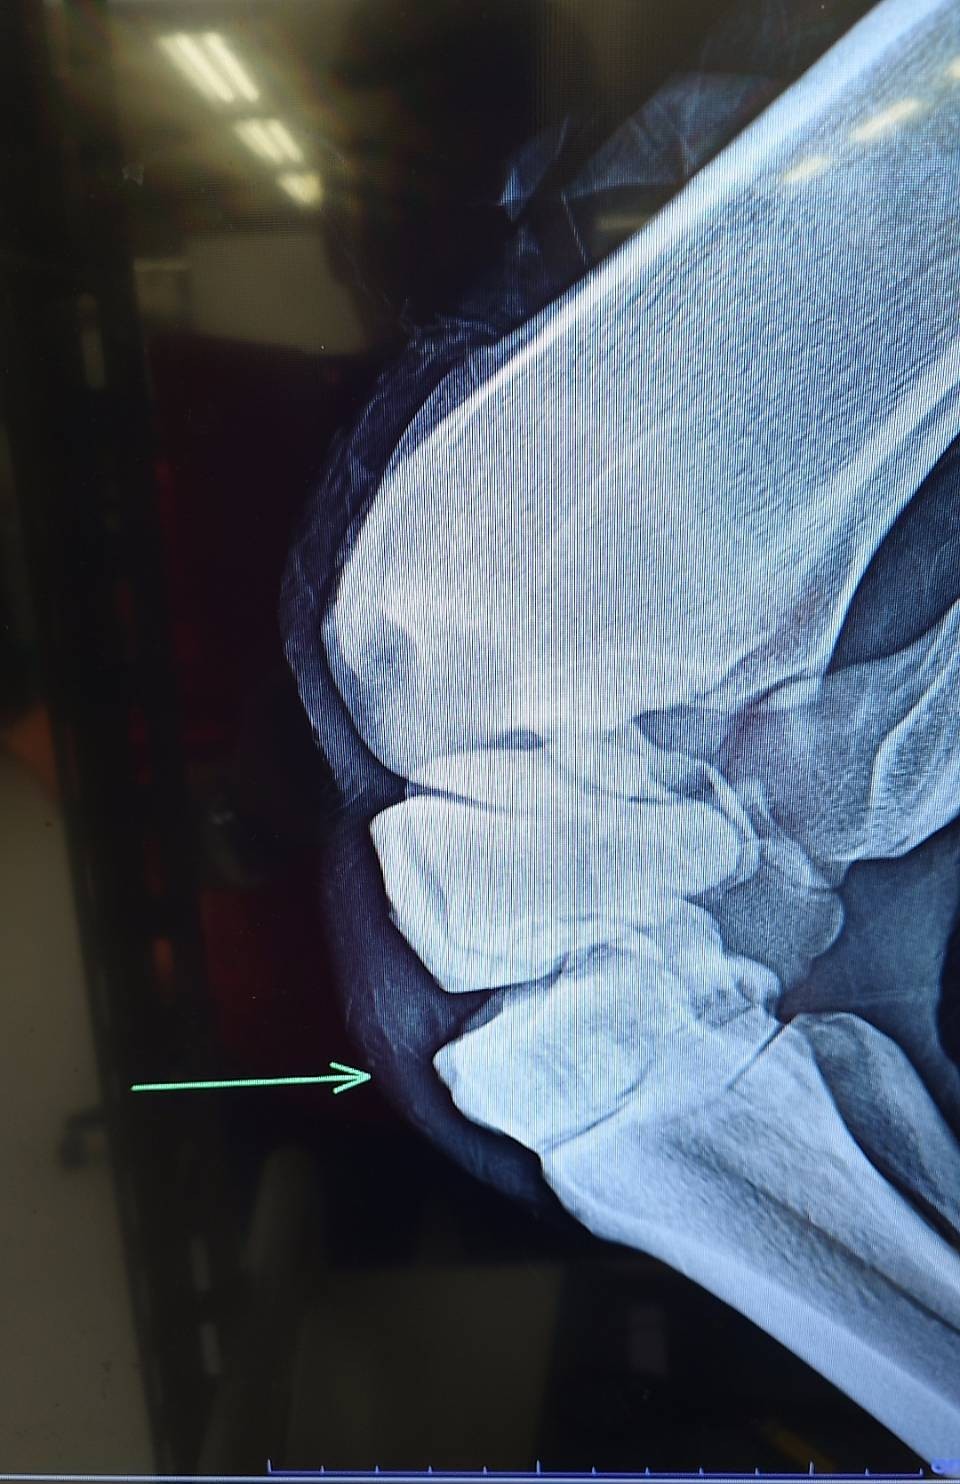

前走で左第3手根骨剥離骨折を発症してしまいました。骨片除去手術を実施し、見舞金9号(競走中6カ月)を適用したうえ、オークション出品となります。

※2026年2月28日の競走で、左第三手根骨剥離骨折を発症。事故見舞金9号(競走中の事故により事故発生の日から6カ月以上出走できなくなった場合)を受給しています。骨片除去手術を実施しています。